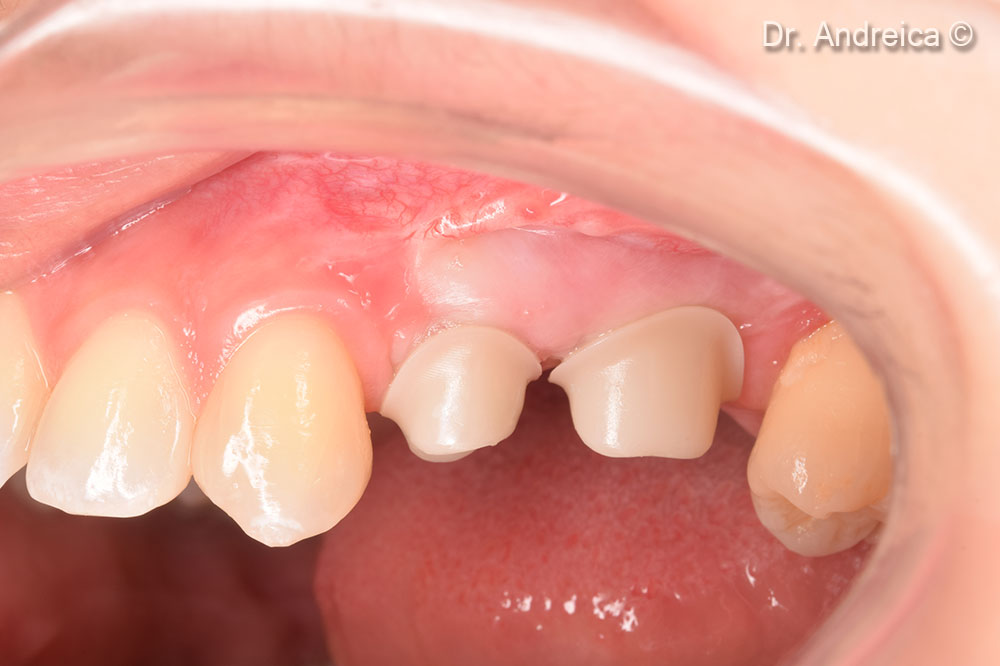

Repositioning the vestibule and increasing the keratinized tissue with a free gingival graft

Developing of the emergence profiles after tissue healing